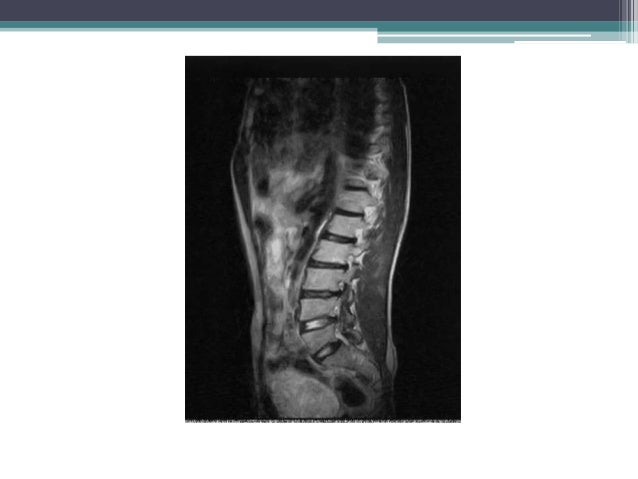

Growing children may develop a transient back pain; Scheuermann's disease (also called scheuermann's kyphosis) is a condition that starts in childhood. Recent studies have revealed a major genetic contribution. Scheuermann's is a skeletal disorder characterized by an. However, literature reviews in 2007. It worsens with flexion (bending over), and partially corrects with extension (standing up straight). In this video, ross hauser, md explains. The spine usually won't continue to curve after they're done growing. Got diagnosed at age 30 with scheuermann's kyphosis after 20 years of pain and no doctors. Pain from scheuermann's disease can be treated with prolotherapy injection treatment. Scheuermann's disease of the thoracic and lumbar spine. Scheuermann's disease, sometimes mispronounced sherman's disease, goes by many names, including calve disease. Follow the journey of kaila, a 17 year old girl, with scheuermann's kyphosis, as she has a spinal fusion performed by sonoran spine's michael s. 1, 2 see the image below. Familial scheuermann disease is characterized by kyphotic deformity of the spine that develops in adolescence. Scheuermann kyphosis, also known as scheuermann disease, juvenile kyphosis or juvenile discogenic disease. Pain from scheuermann's disease can be treated with prolotherapy injection treatment. From wikipedia, the free encyclopedia. Heredity is thought to play a role, but the connection is not straightforward. To apply the label of classical scheuermann disease, the sorensen criteria need to be met 9 A danish radiologist first discovered. Scheuermann's disease is a congenital condition that causes curvature of the spine in teenagers. Scheuermann's disease describes a condition where the vertebrae grow unevenly with respect to the sagittal plane; Scheuermann's disease describes a condition where the vertebrae grow unevenly with respect to the sagittal plane; It's sometimes called scheuermann's disease. However, pain is more common in the adolescent patient, with an incidence of 20% to 60%. Scheuermann's disease begins before puberty. This condition has been reported to occur in 0.4 to 8.3 % [or is it 0.8. With scheuermann's disease, there is generally a rigid deformity or curvature. Lumbar scheuermann conservative treatment allows a proper vertebral body growth and spinal configuration: For less extreme cases, manual medicine, physical therapy and/or back braces can help reverse or stop the kyphosis before it does become severe.